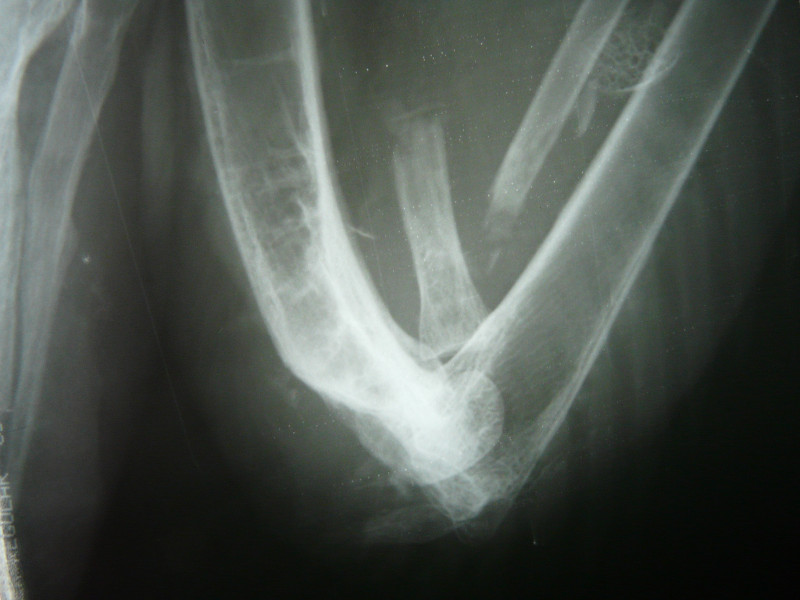

El primero, un ejemplar adulto de milano real ingresó muy aturdido pero con buena condición corporal, lo que nos hizo sospechar que la lesión era reciente. Un gran hematoma invadía toda el ala izquierda y encontramos algunos orificios pequeños en la piel. Se hizo una radiografía para ver el tipo de fractura (hallamos 2 fracturas en vez de una) y si era necesaria o viable la intervención quirúrgica, encontrándonos varios perdigones y numerosos fragmentos de metralla distribuidos por toda el ala y resto del cuerpo. Se aplicaron primeros auxilios y vendaje para inmovilizar la fractura que, afortunadamente, estaba alineada. Gracias a la fluidoterapia y cuidados intensivos el animal se estabilizó y a día de hoy se alimenta con normalidad y su comportamiento es el adecuado. Permanecerá con el vendaje puesto hasta la próxima semana, cuando haremos una radiografía de control para ver si hay formación de callo óseo, podemos retirar el vendaje y valorar el resultado tras este mes en la Enfermería. Se transferirá al departamento de Rehabilitación para empezar con fisioterapia y ver cuáles son las posibilidades reales de liberación de este ejemplar.